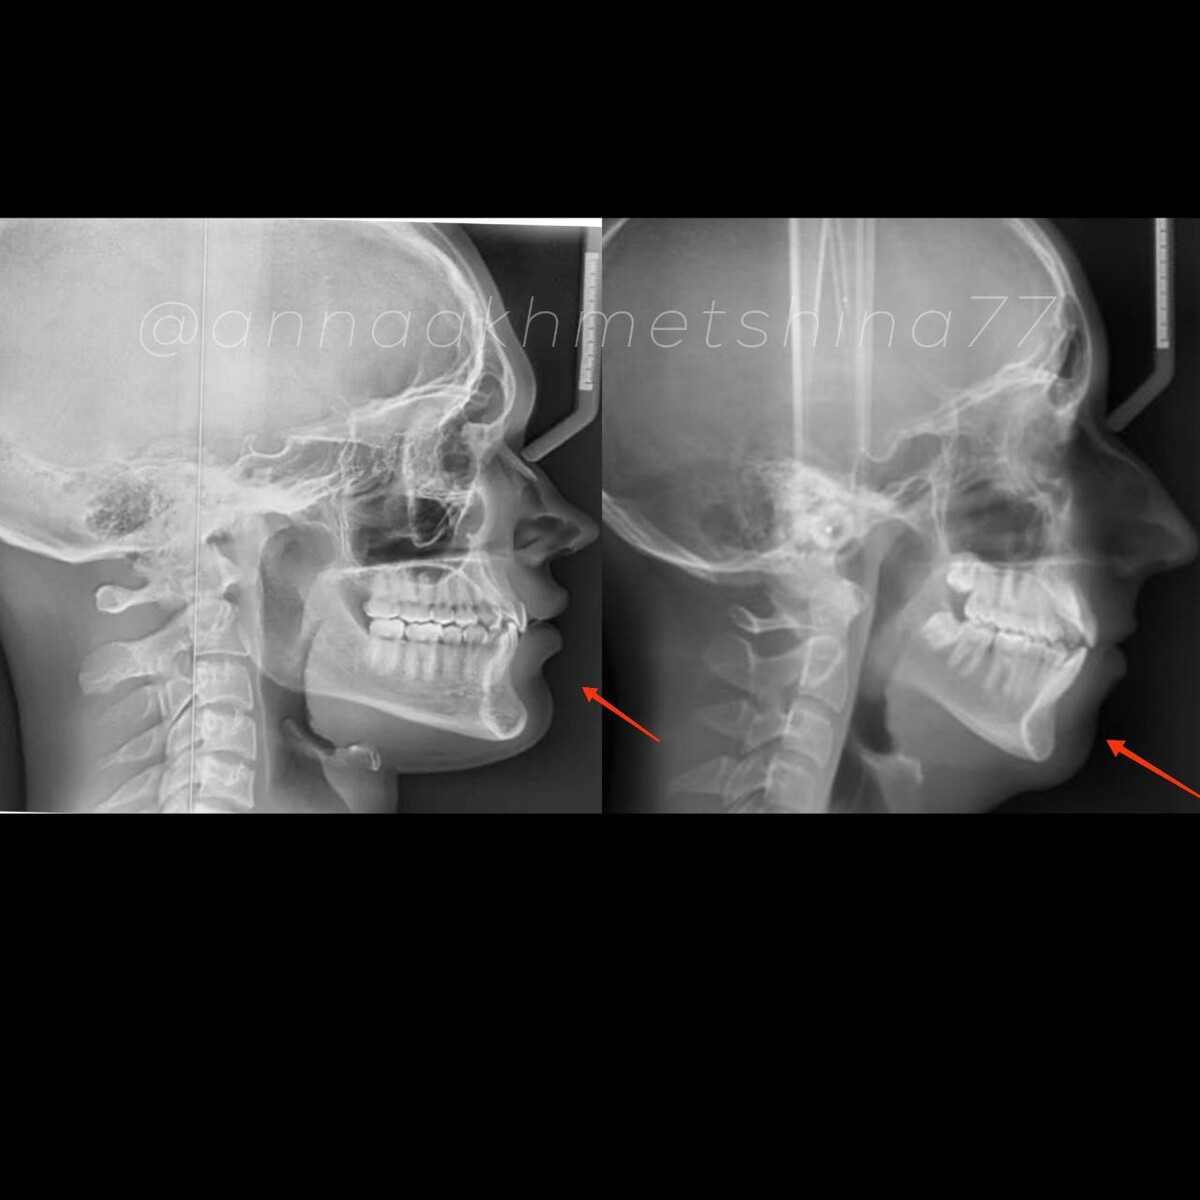

Чем вертикальнее лицевое развитие и чем больше челюсть стоит под наклоном - тем больше будет это расстояние, особенно если нч достаточно массивная сама по себе.

При мезиальном скелетном прикусе (на рисунке) подбородок тоже длинный и массивный, а нижняя челюсть хоть и впереди - стоит под сильным углом.

И таки да, проблема мезиального прикуса вовсе не в излишне большой нижней челюсти, как многие думают, а в недоразвитии верхней.

При изменении углов наклона челюстей эти расстояния визуально меняются, а мышцы подбородка расслабляются.